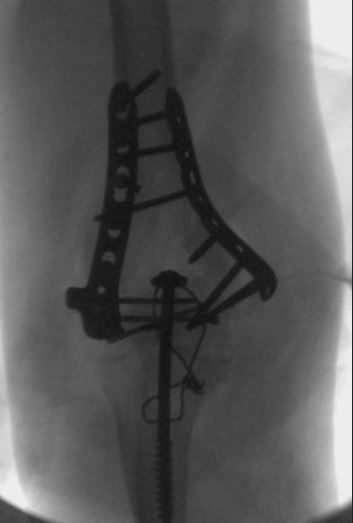

What is the most common complication of the fracture seen in figure A, if operatively treated as seen in figure B?

A

decreased elbow range of motion